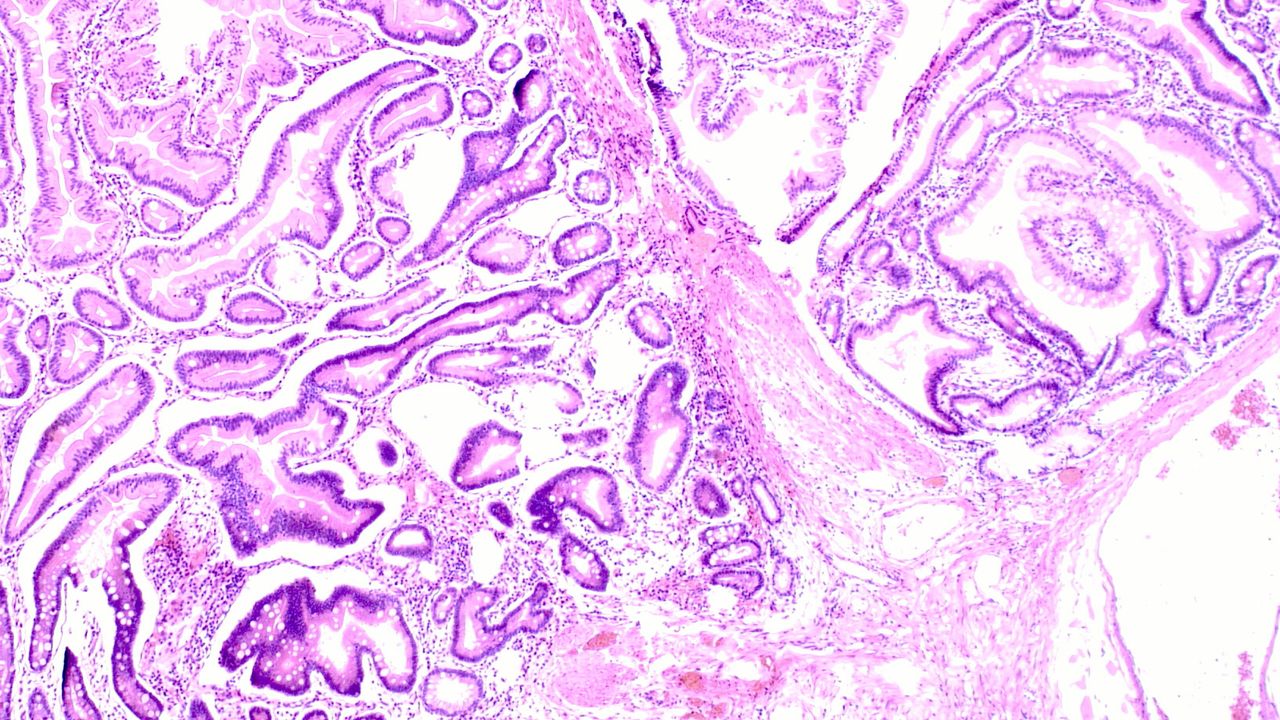

Peutz–Jeghers sendromu (PJS), sindirim sisteminde özellikle ince bağırsakta hamartomatöz polipler ve dudak ile ağız çevresinde koyu lekelerle seyreden nadir bir genetik hastalık olarak tanımlanıyor. Hastalığın STK11 adlı gende meydana gelen kalıtsal mutasyonla ilişkili olduğu bildiriliyor. Uzmanlara göre sendrom çocukluk veya genç erişkinlik döneminde belirti verebiliyor ve karın ağrısı, bağırsak tıkanması, kanama ve kansızlık gibi şikayetlere yol açabiliyor.